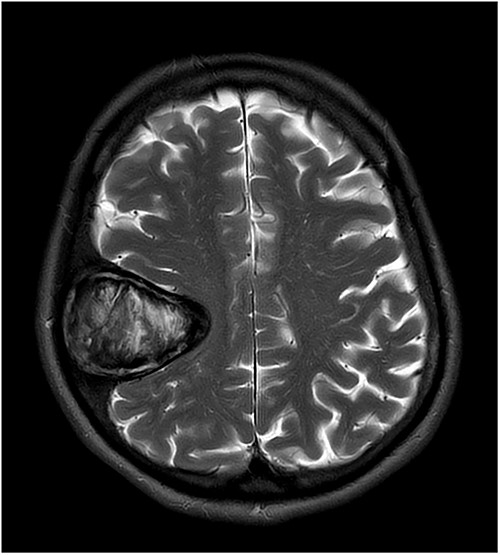

Our patient is a 76-year-old gentleman with medical history of hypertension and lumbar spondylosis. He did not have any previous history of trauma or systemic infections. He had presented to his local hospital with a 2-day history of left arm numbness. He did not report any headaches or giddiness. On clinical assessment, he did not have any neurological deficits. A CT brain and MRI brain (Figs 1–5) with contrast revealed a 53 × 53 × 41 mm partially calcified, heterogeneously enhancing conical shaped right extra-axial parietal convexity lesion. The overlying calvarial bone was remodelled and possibly eroded. There was evidence of prior haemorrhage within the lesion and scattered internal and peripheral calcification. Based on these characteristics, the possible diagnoses were that of an intraosseous meningioma, haemangioma and giant cell tumour. Patient was consented for craniotomy and excision of the tumour.

T2-weighted axial MRI scan showing the lesion with intralesional haemorrhagic products. There is no evidence of dural invasion.